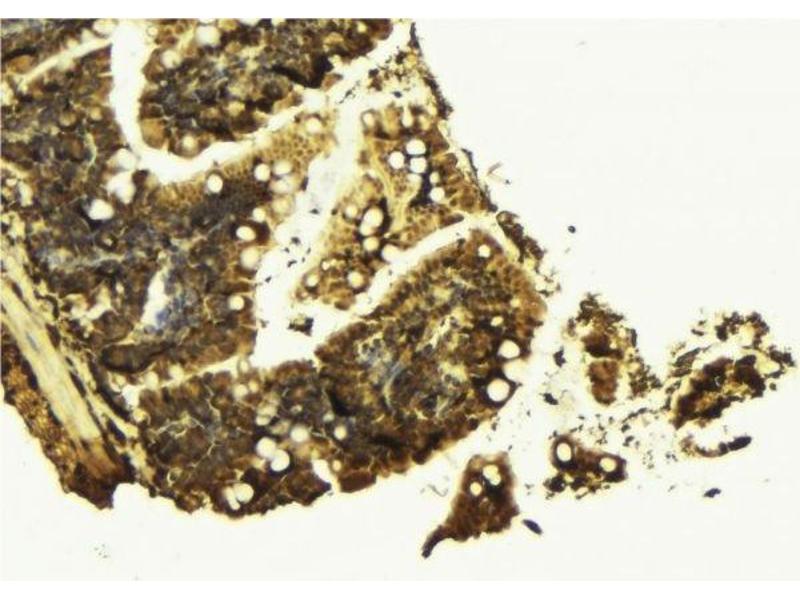

Choisissez l’un des 247 anticorps CTNNB1 de notre liste de produits basés sur 68 publications et 314 images de validation.

Découvrez des anticorps CTNNB1 fiables issus d’une large sélection de fabricants renommés. Notre portefeuille permet une détection précise de CTNNB1 dans plusieurs espèces, y compris Human, Mouse, Rat, Dog, Monkey, Chicken, Cow, Zebrafish (Danio rerio), Pig, Horse, Rabbit, Xenopus laevis, Hamster, Bat, Guinea Pig, Sheep, Opossum, et prend en charge diverses applications de recherche telles que WB, IHC, ELISA, IF, FACS.